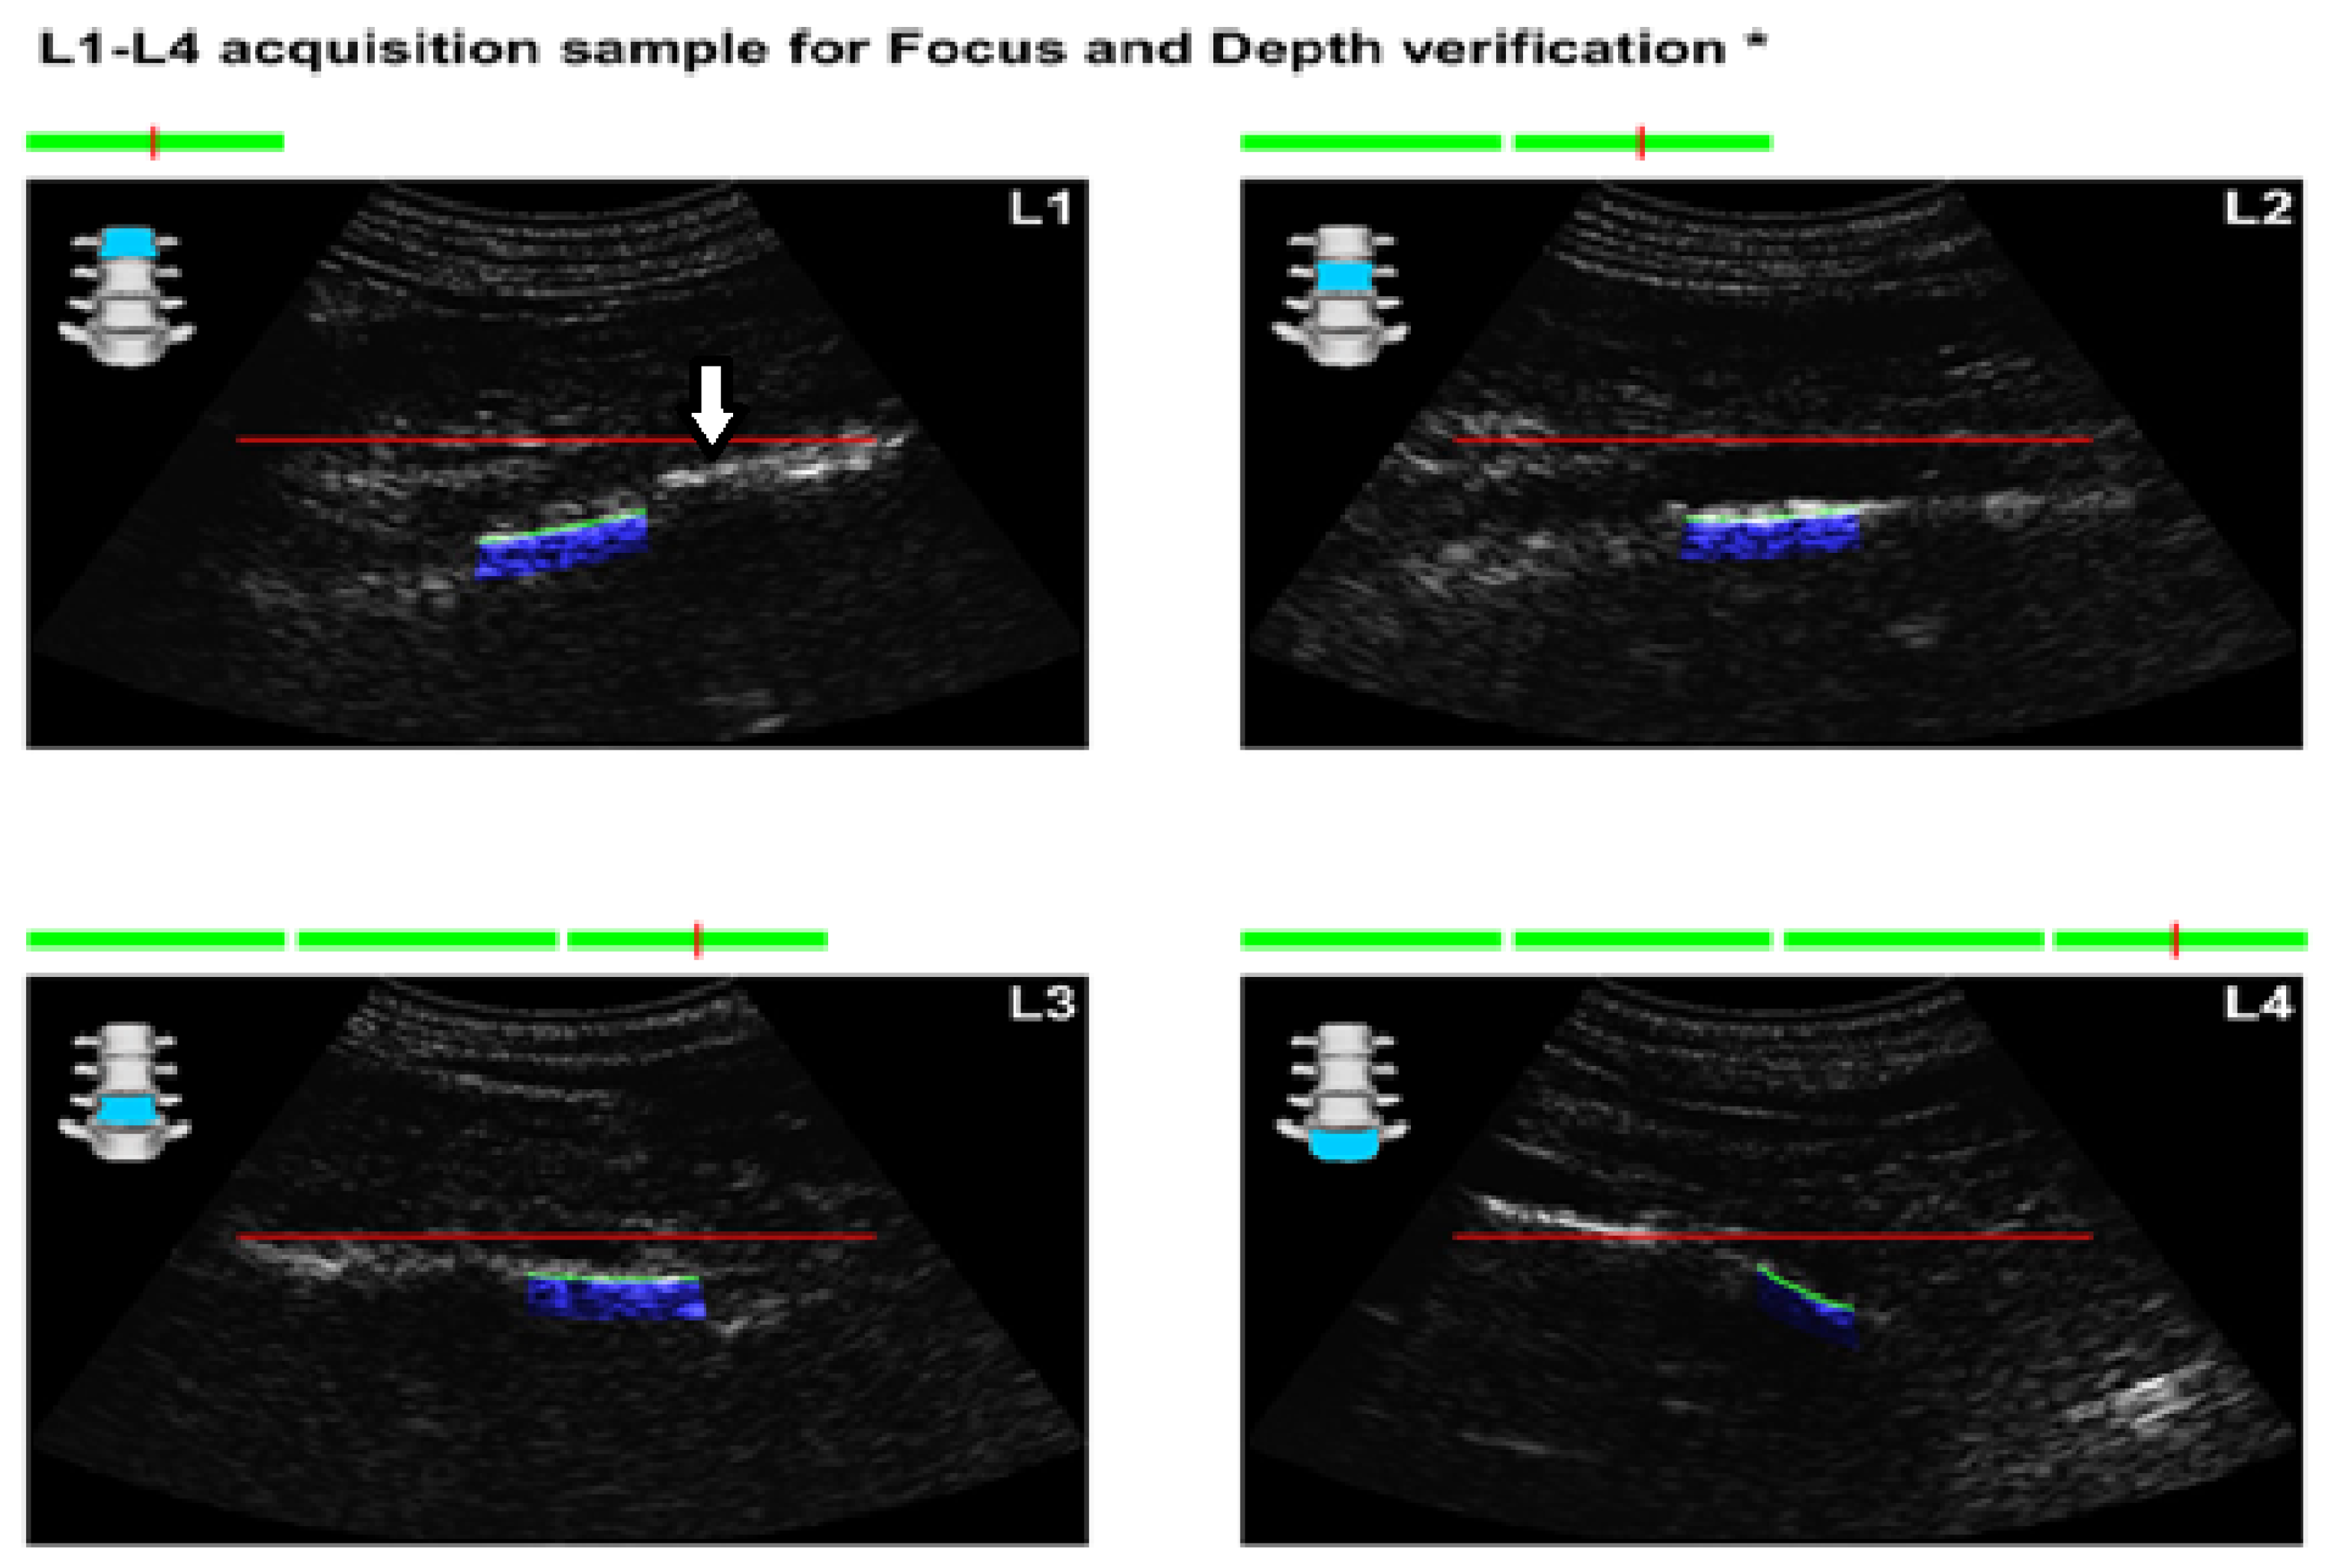

1.3. Signal Acquisition

1.4. Spectral Analysis and Reference Model Comparison